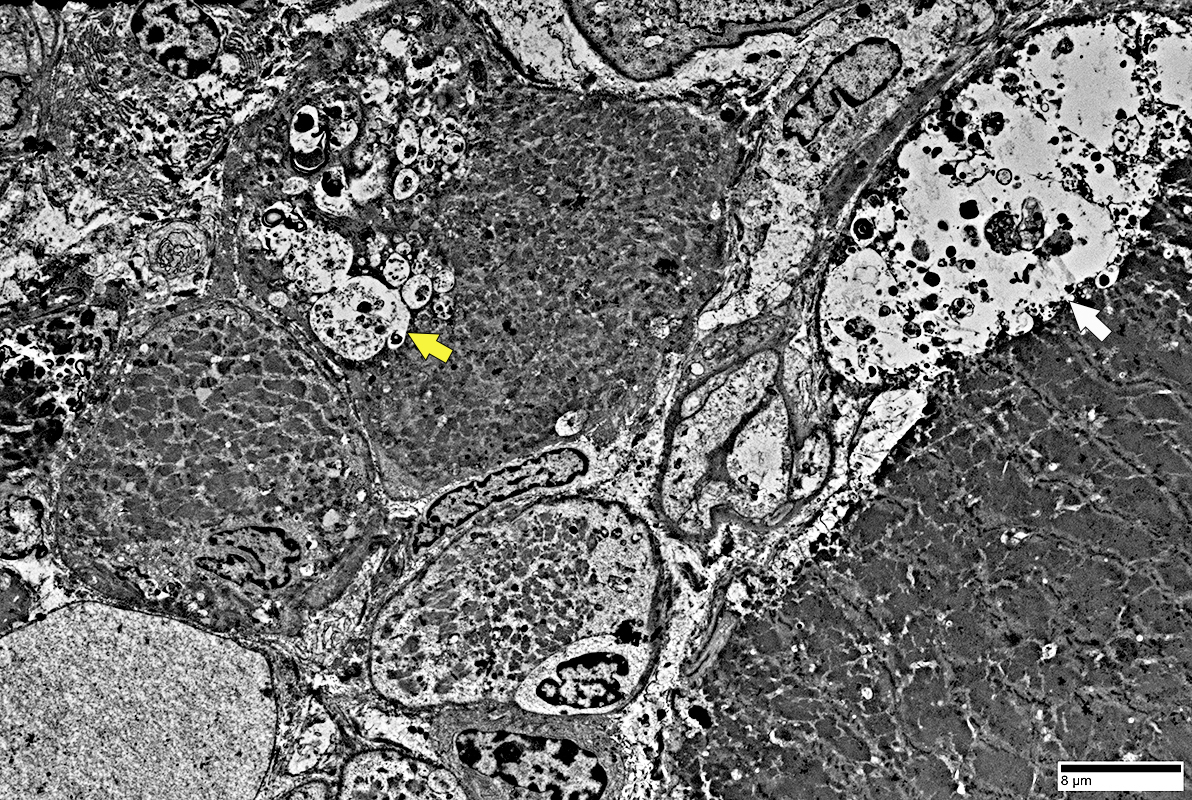

Muscle fibers: Focal Invasion by Cells

Inflammatory cells & Focal invasion of Muscle fibers in IM-VAMP (IBM)

Lymphocyte, Large, Possibly Granular (Black Arrow)

Extends a process (White arrow) into a non-necrotic muscle fiber

Other lymphocytes & histiocytes

Whole immune cells may be invading muscle fiber

Present in extracellular regions around muscle fiber

Muscle fiber pathology

Aggregates, various types

Vacuoles

Muscle fiber: Focal Invasion by Cell

Lymphocyte, single, invades muscle fiber

Lymphocyte location: Inside muscle fiber; Above sarcolemma; Neighbors myonucleus

Muscle fiber: Focal Invasion by Cells

Lymphocytes (Light cytoplasm) & Histiocytes (Dark cytoplasm with phaogcytic debris)

Within the muscle fiber

Closely apposed to each other

Also in extracellular space

Sarcomeres near invading cells: Normal structure

Muscle fiber: Focal Invasion by small cell processes

Lymphocyte: Focal Invasion of a Muscle Fiber (Arrows)

Muscle fiber structure is damaged